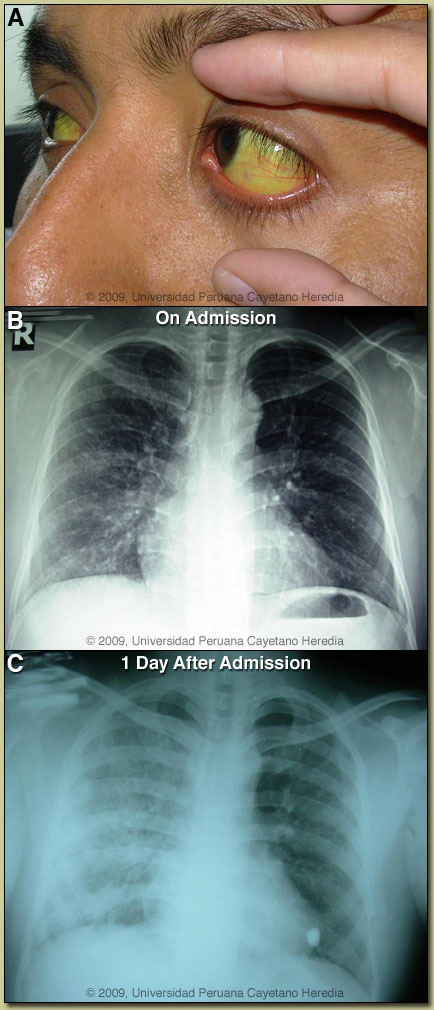

| Diagnosis: Leptospirosis. |

| Discussion: Serology by the Microagglutination technique (MAT) for leptospira: 1:800 for L. icterohemorrhagiae Copenhageni (M20), 1/200 for L. i. iceterohemorrhagiae RGA and L. i. Mankarso (these titers are considered weakly positive). An IgM ELISA for dengue taken of day 3 of illness was positive. In acute dengue IgM does not usually turn positive until day 5-7 and then remains positive for several months. As the clinical picture (jaundice, renal, and pulmonary involvement) and pattern of hepatic function abnormalities here is not consistent with dengue, the positive IgM was felt to reflect an earlier episode of dengue likely from the visit to Pucallpa 2 months earlier.

Leptospirosis needs to be considered in the differential diagnosis of any undifferentiated tropical fever. It has protean clinical manifestations and at differing stages of the illness may be impossible to distinguish clinically from yellow fever, dengue, rickettsial disease, typhoid, malaria, brucellosis, tuberculosis, or viral hepatitis. Typically, leptospirosis is described as having an initial septicemic phase, which may be mild, with fever, myalgia, headache, conjunctival suffusion [see Image A], and abdominal wall pain. Our patient had the conjunctival suffusion but not the muscle tenderness in calves and lumber areas often described as distinguishing features of leptospirosis. The illness is often self-limited but in some cases, after an apparent recovery, may present a biphasic illness and progress to an immune stage manifest by fever, meningitis, and uveitis. The two distinct stages may be obscured and run together in severe disease (Weil’s Disease) manifested by the classic defining triad of jaundice, hemorrhage, and renal failure. Weil´s disease has a mortality of 10%. The true incidence of pulmonary involvement is unclear, appears to have increased in recent years, and may be as high as 70%. Patients may present with symptoms ranging from cough, dyspnea and hemoptysis to ARDS [Clin Infect Dis. 2005 Feb 1;40(3):343-51]. The present case shows a typical radiographic evolution that is thought to represent intra-alveolar and interstitial hemorrhage [Braz J Infect Dis. 2007 Feb;11(1):142-8]. Pulmonary involvement has emerged as the main cause of death due to leptospirosis in some countries. Jaundice and bilirubinemia out of proportion with hepatocellular damage is the usual finding in leptospirosis. This is manifest as significant jaundice in the face of an SGOT and SGPT that is no more than 3-4X normal with an alkaline phosphatase that may be as high as 10X normal. The mechanism of the cholestasis in leptospirosis is not entirely clear. In severe or prolonged disease, renal damage will occur and the sediment is usually active. Non-oliguric hypokalemic renal failure as found in this case is characteristic. Progression to oliguric renal failure would be predictive of higher mortality. Isolation of Leptospira in culture is difficult and insensitive. Culture in special media in tubes held at 28-30°C for prolonged periods is necessary. Blood is only positive in the first week of illness after which urine becomes progressively more positive. Cultured leptospires are only visible and confirmed using dark-field microscopy. Diagnosis is most often serological and retrospective [MAT], IgM ELISA, or a commercially available rapid dipstick test. Leptospirosis is endemic in almost every country but more so in the tropics. Traditionally an occupational disease and a disease of poverty in peri-urban slums, it has also emerged as a disease of adventure travelers (hikers, bikers, boaters, swimmers) that have contact with standing or moving water. Leptospires may penetrate conjunctiva, macerated skin, or possibly the oropharynx. Leptospirosis is maintained in the environment by long-term carriage and excretion of the organism from the urinary system of asymptomatic animal carriers. Rodents are most frequently implicated with swine, cattle, and dogs next most frequent, but the full spectrum of mammals forming the reservoir is unclear. Classification of leptospires is complex and obscure to most clinicians. While most human isolates are L. interrogans, further division into a number of species using DNA relatedness is hampered by a traditional naming system that uses serologically defined antigenic determinants (serovars and serogroups) that may be shared by two or more species. Recent trials support the use of intravenous antibiotics for severe disease. Cefotaxime or ceftriaxone are equivalent to penicillin and much more convenient due to once daily dosing [Clin Infect Dis. 2003;36(12):1507-13.; Clin Infect Dis. 2004;39(10):1417-24.]. Milder disease may be treated with oral doxycycline. Efficacy appears best when treatment is begun within 4 days of illness onset. There was a marked dissociation between the significant laboratory abnormalities and the patient’s appearance. He was treated with IV ceftriaxone (1gm/d for 10 days). The dyspnea and low-grade fever resolved after 4 days and the myalgia for 5 more days. Jaundice normally takes longer to resolve but the renal function normalized by Day 3.